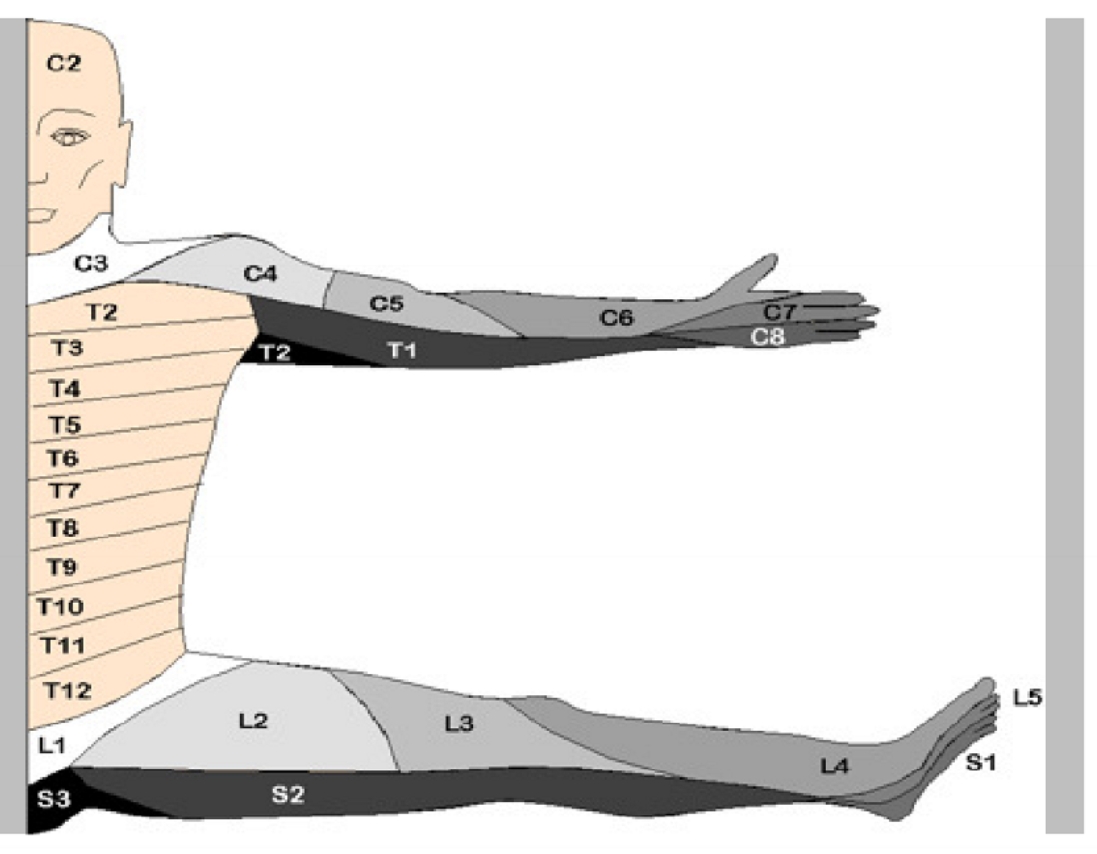

dermatoom

= uncartrose C6-C7 (links)

klachten: cervico-brachialgie

blauw gedeelte = osteofiet

pijn straalt uit naar 2e, 3e en radiale helft 4e vinger